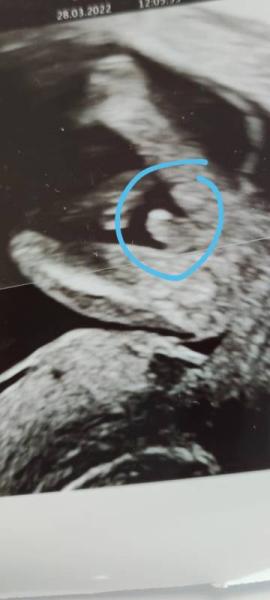

Huhu, Hab heute eine Tendenz von 99% bekommen. Würde gerne mal eure Tendenz wissen

Bild zu Mädchen oder Junge? :) - Schwanger - wer noch? Rund um die Schwangerschaft

Ich würde mich da jetzt garnicht festlegen, das was man da sieht kann ja auch ein Ärmchen/Händchen sein. Tatsächlich würde ich sagen ihr bekommt ein kleines Mädchen, aber ich bin auch nicht vom Fach

Was sagt den die Tendenz ? Ich würde junge tippen

Die 16. ssw ist noch zu früh, mir wurde auch gesagt und gezeigt (in der 16.ssw ) das es ein junge wird zu 90% im nächsten termin (20.ssw) ups ein Mädchen hab auf den darauf folgenden Termin gewartet um sicher zugehen, ist eindeutig ein Mädchen Also ich wäre noch ein bisschen geduldig an deine stelle, muss aber natürlich nicht das selbe heißen bei dir, nur weil es bei mir so war Alles Gute

Der Arzt meinte in fast jedem Winkel wie das Baby sich bewegt hat im Ultraschall sieht es nach einem Jungen aus. Aber ja kann sich natürlich immer noch ändern Aber wenn es sich noch ändern sollte, nicht schlimm, beides ist für mich völlig in Ordnung. Die Hauptsache ist ja immer noch das unsere Kleinen gesund auf die Welt kommen Danke und liebe Grüße